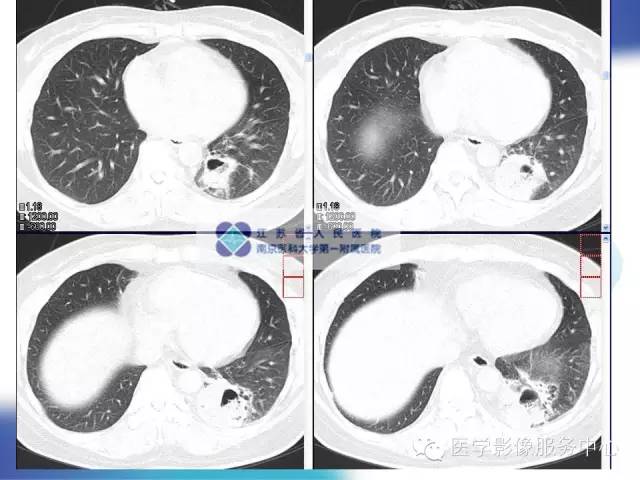

【病例】肺隔离症1例CT影像表现

女性,36岁。反复发热、咳嗽、咳痰一年。

X线:肺叶内型表现为圆形、卵圆形团块影或下野不规则渗出性斑片影,肺叶外型表现为三角形分叶状影。病变多位于左肺下野,边界清楚、密度均匀增高,合并感染后与支气管相通,可形成单发或多发含气囊肿,甚至出现气液平面,密度不均匀,边界模糊。

CT:主要表现为三种类型:含有气体和液体的囊肿或软组织肿块;围绕囊肿或肿块周围的肺气肿改变;局限性肺多血管征。病变周围肺组织还可伴有支气管扩张,肺组织实变等。增强扫描病变实质可见轻度或明显不规则强化,囊性病灶可见环形强化,结合图像后处理技术( MPR、MIP、VR)多可见异常供血动脉及引流静脉,在一定程度上可以取代动脉造影。隔离肺组织供血动脉多为胸主动脉和腹主动脉,少数为隔下动脉、肋间动脉、脾动脉等。引流静脉多为肺静脉。